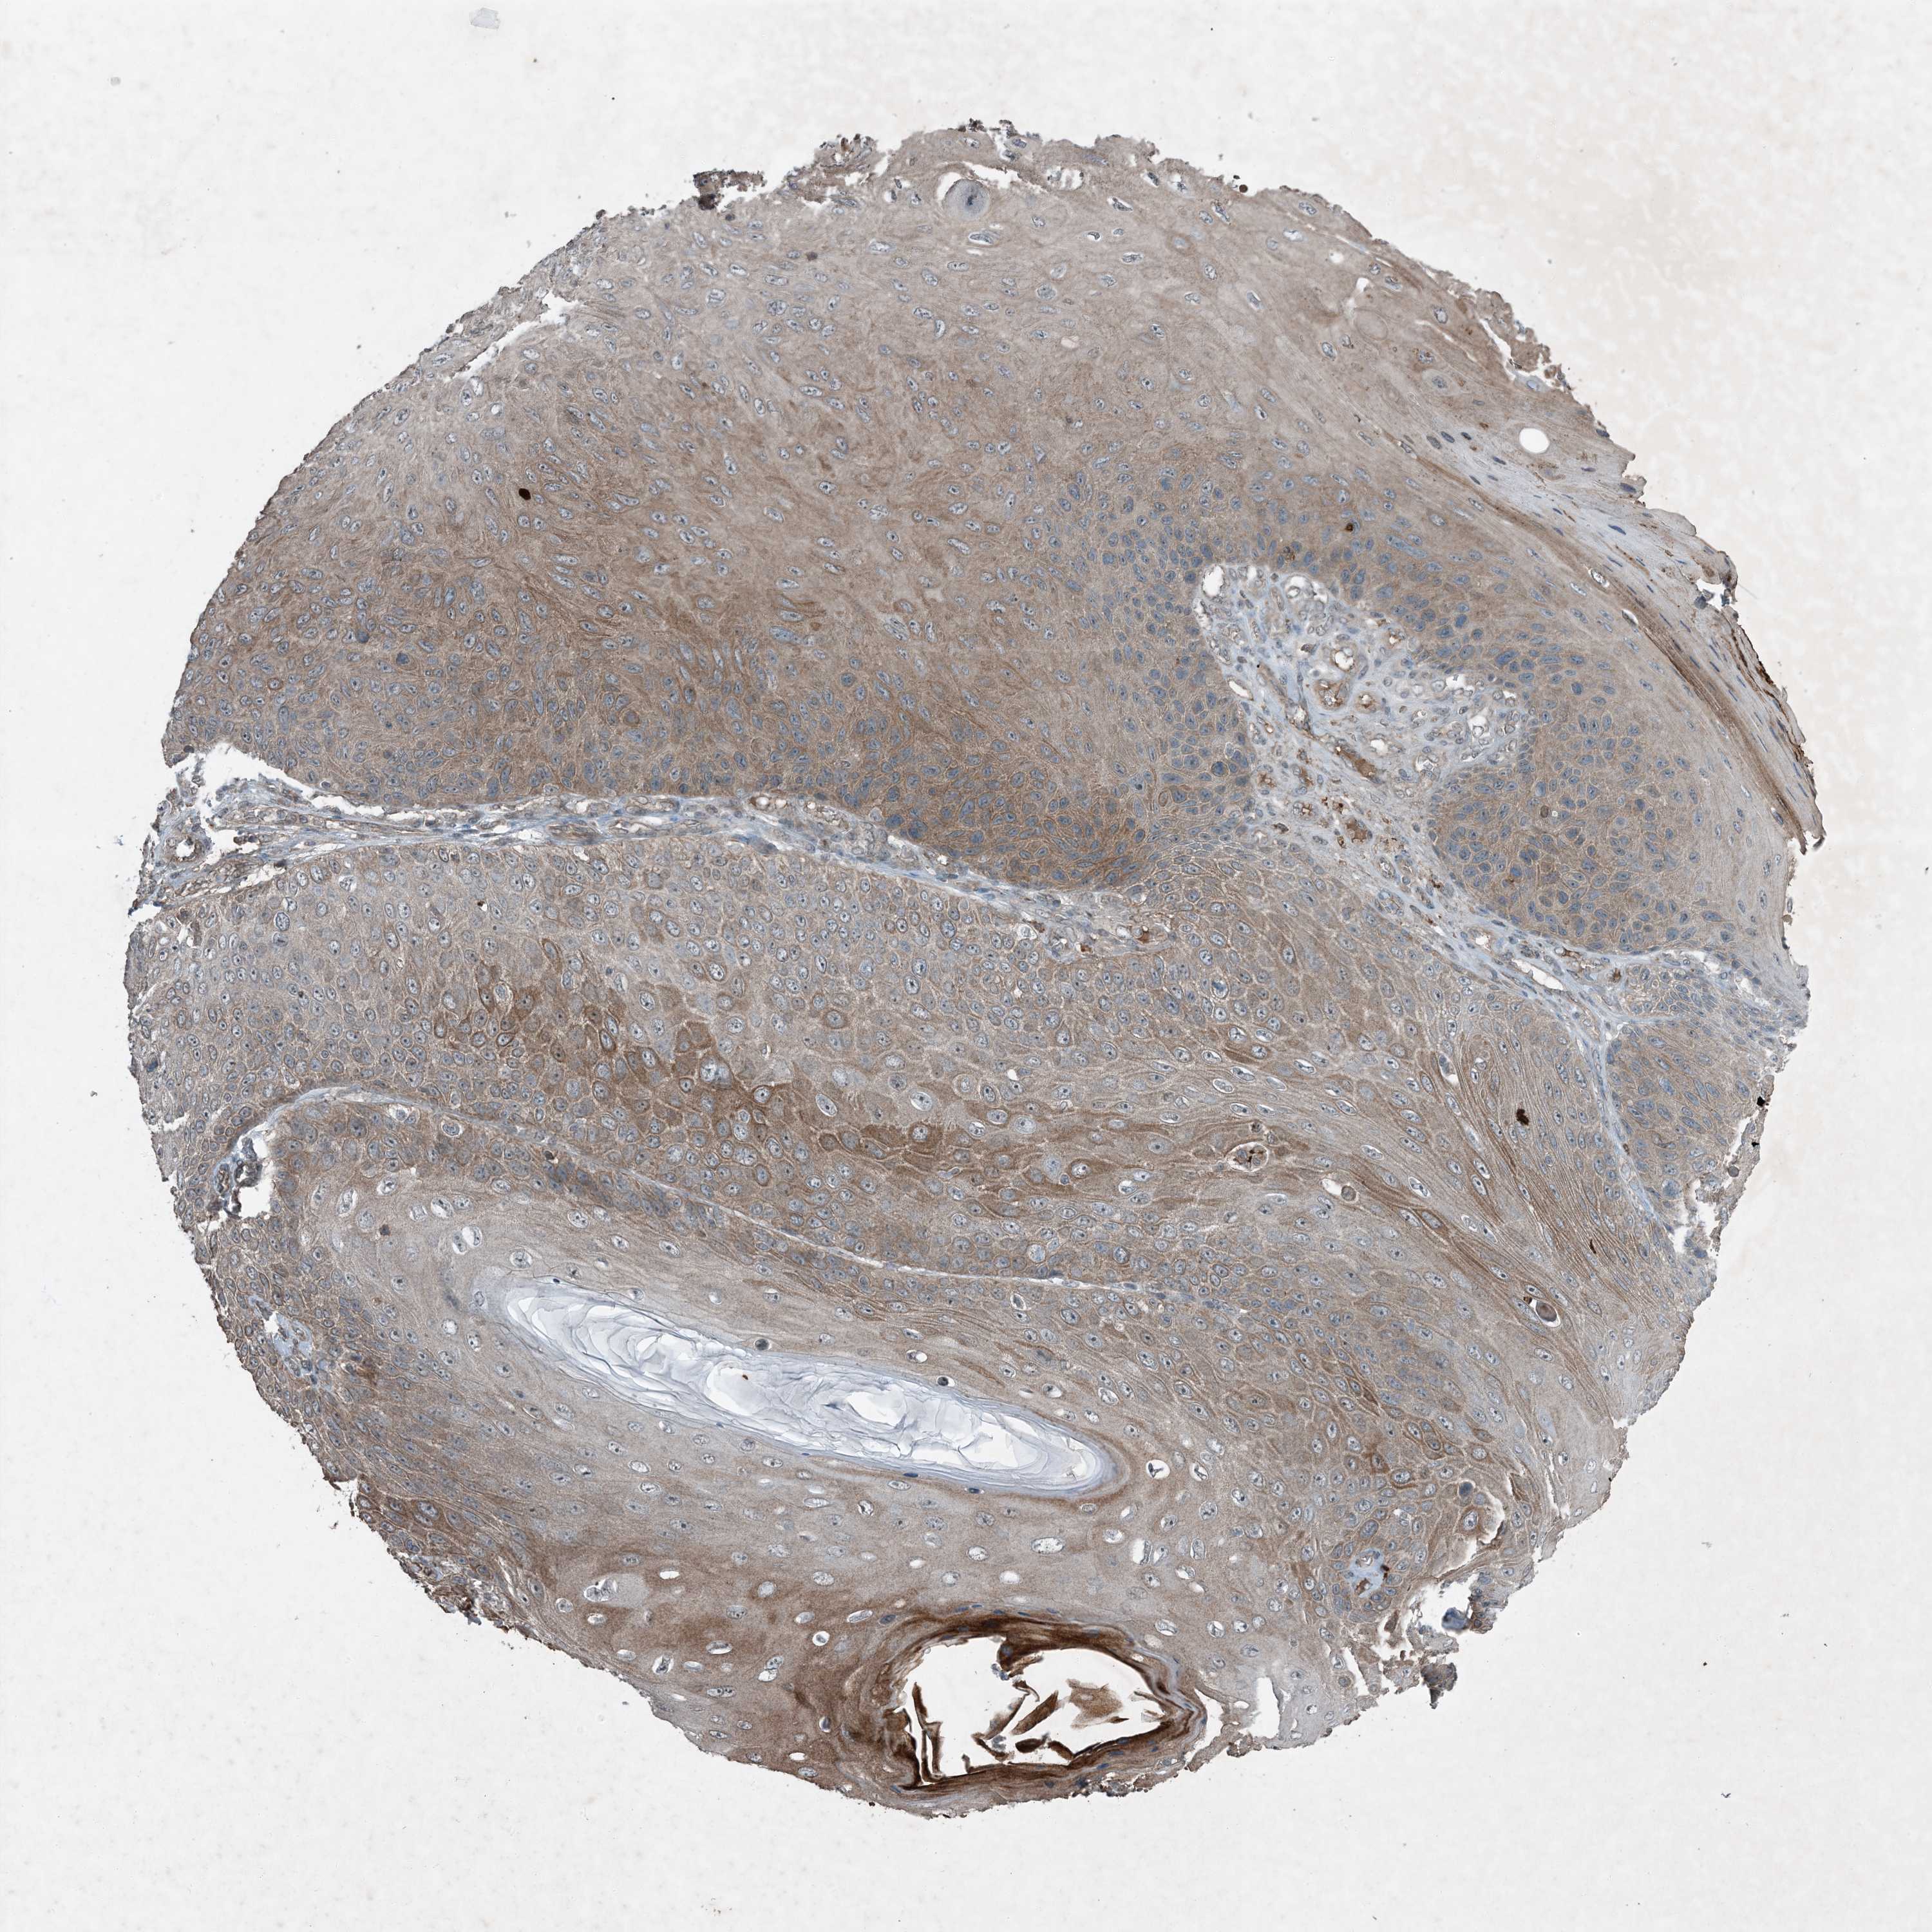

SKIN CANCER - Protein expressioni

A mouse-over function shows sample information and annotation data. Click on an image to view it in a full screen mode. Samples can be filtered based on level of antibody staining by selecting one or several of the following categories: high, medium, low and not detected. The assay and annotation is described here.

Antibody staining in the annotated cell types in the current human tissue is reported as not detected, low, medium, or high, based on conventional immunohistochemistry profiling in selected tissues. This score is based on the combination of the staining intensity and fraction of stained cells.

Each image is clickable and will lead to virtual microscopy that enables deeper exploration of all samples and also displays staining intensity scores, fraction scores and subcellular localization as well as patient and tissue information for each sample.

Antibody HPA029669

Squamous cell carcinoma, NOS